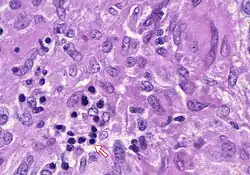

In pathology, a Councilman body, also known as a Councilman hyaline body or apoptotic body, is an eosinophilic globule of apoptotic hepatocyte cell fragments. Ultimately, the fragments are taken up by macrophages or adjacent parenchymal cells.[1] They are found in the liver of individuals suffering from acute viral hepatitis, yellow fever, and other viral syndromes.[2]

Hepatocytes are the liver's primary parenchymal cells, forming 80% of the liver's mass and 60% of its cells. They are round in shape and contain a nucleus and organelles that contribute to metabolic and secretory functions.[5] Hepatocytes also play a pivotal role in liver inflammation.[6] Councilman bodies are often named for the hepatocytes undergoing apoptosis, which occurs in the portal tracts and lobules of the liver. Inflammation of the liver is caused by the cytotoxic killing of hepatocytes, or Councilman bodies. Eventually, this inflammation leads to liver damage in viral hepatitis.[7] Through the use of double immune fluorescence methods, HBsAg and/or HBcAg (hepatitis B core antigen) are present in Councilman bodies in the liver.[8]

With a bright field microscope, Councilman described typical, discrete, necrotic lesions in human hepatic cells of those infected with yellow fever.[9] He noted that the bodies appeared to be red in hematoxylin and eosin-stained sections of hepatic tissue, while being circumscribed, varying in size, round or irregular shape, and having numerous vacuoles of different sizes.

Five adults with hepatitis, two children with hepatoma, and three mongrel dogs provided tissue samples for study have an auxiliary liver transplant into the pelvis. The tissues were fixed immediately in ice-cold 1% osmium tetroxide, buffered with veronal acetate, and sucrose. Sections were cut, stained with lead hydroxide or citrate, and viewed under an electron microscope. The results showed the both canine and human tissue were intact, but altered hepatocytes were observed.[11] The doctors declared that councilman bodies were observed as vacuolated acidophilic bodies within the tissue samples.